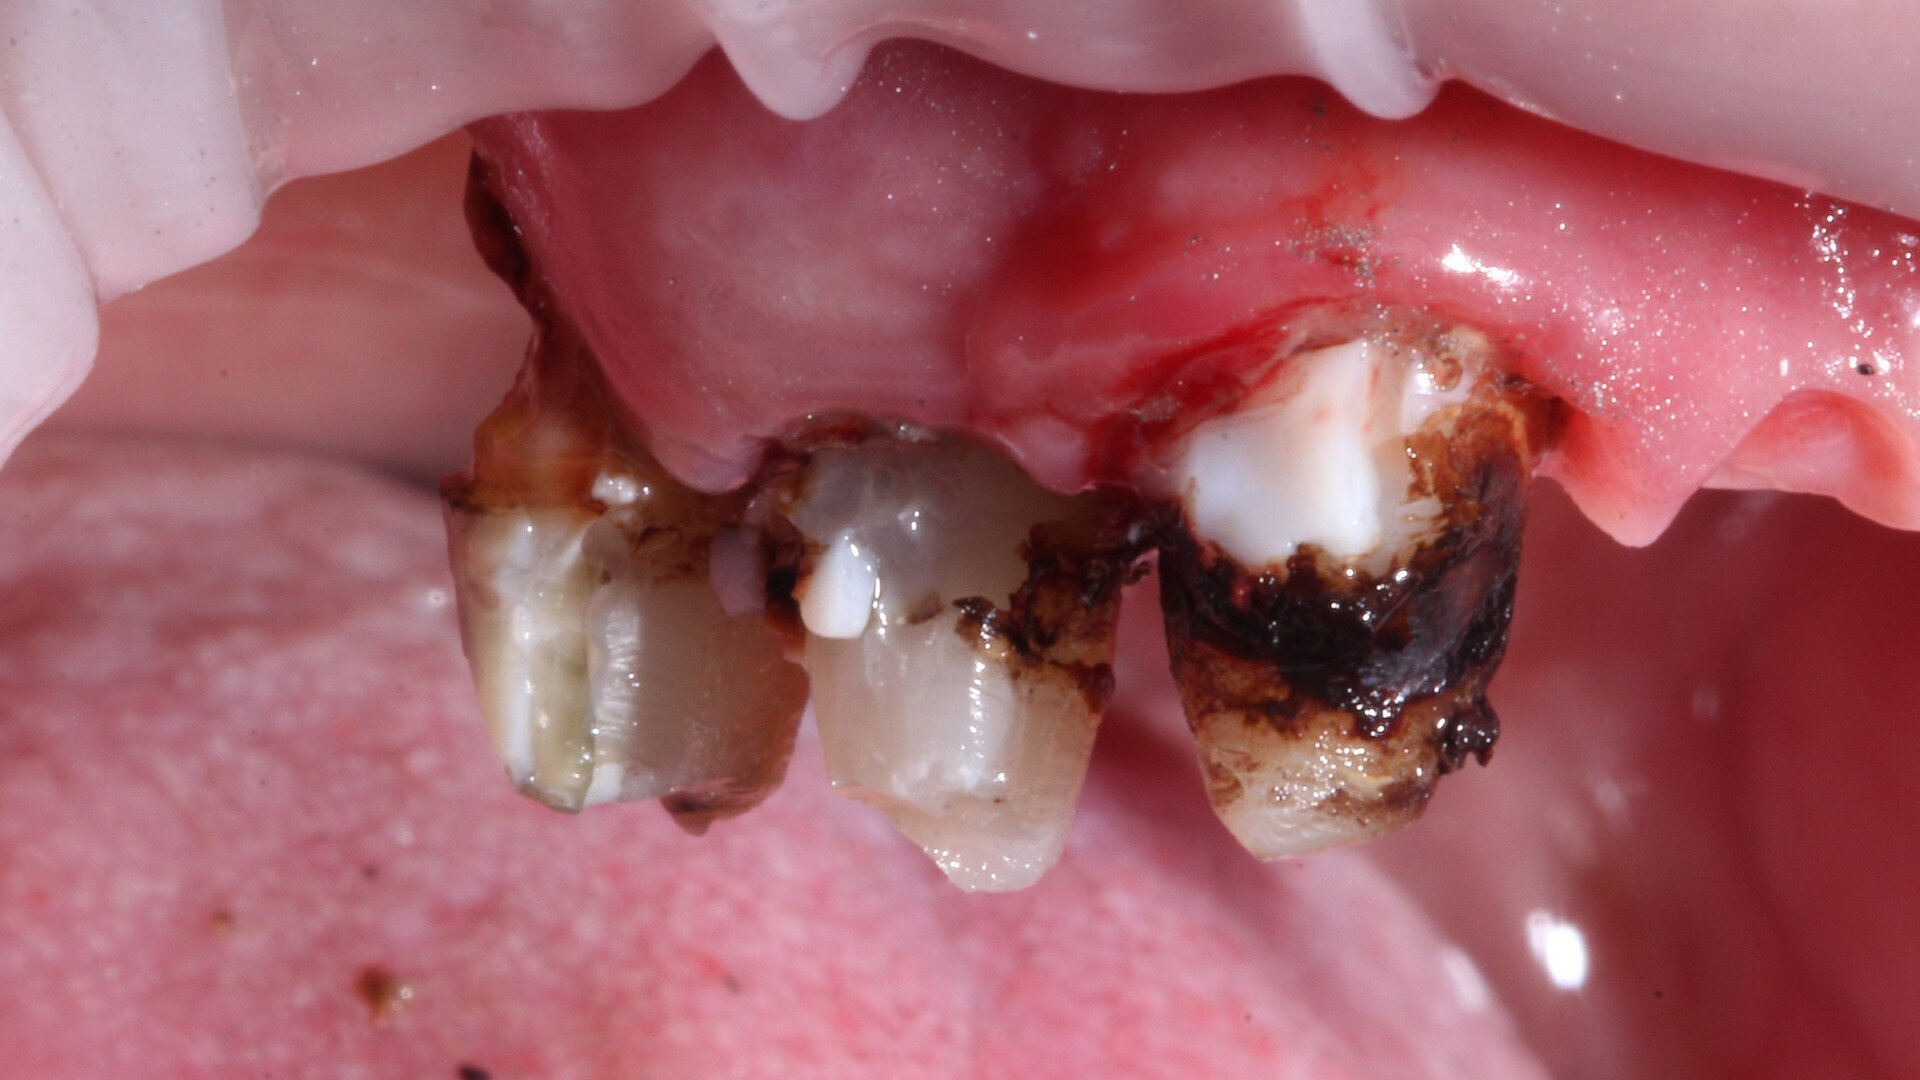

Extraction of severely decayed teeth

The first step in the patient’s dental rehabilitation involved the extraction of severely decayed teeth. This procedure was necessary to eliminate the source of infection and discomfort and to prepare the oral cavity for the subsequent steps in the rehabilitation process. The dentures were later used to simplify the guided surgery planning.5 After the extraction, the patient was provided with appropriate postoperative care instructions, and a healing period was allowed before proceeding with the next steps (Fig. 1).